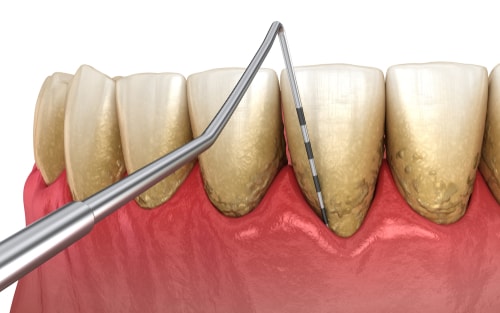

Die Herausforderung für die nächsten Jahrzehnte in der Zahnmedizin ist die Parodontitisbehandlung. Sie stellt die häufigste Ursache für Zahnverlust dar. Doch neben der Prävention, liegt das Augenmerk nun auf die Nachsorge nach Behandlungsabschluss.

Im Verlauf der Zahnmedizin konnte der Kampf gegen Karies sehr erfolgreich geführt werden. Doch im Bezug auf die Parodontitis steht die Zahnmedizin noch am Anfang.

Der Ansatz der Zahnmediziner ist der, das mit der richtigen Vorsorge die eigenen Zähne bis ins hohe Alter erhalten bleiben können. Der Schlüssel zum Erfolg, ist die Beseitigung der Risikofaktoren.

Somit wird klar das eine Sensibilisierung und Förderung der Eigenverantwortlichkeit erfolgen muss. Das bewusst sein für die Volkskrankheit Parodontitis muss geschaffen werden. Auch von zahnärztlicher Seite aus muss die Behandlung strukturiert erfolgen.

- Bei der Kontrolluntersuchung muss das Risiko ermittelt werden und ein Aufklärungsgespräch ggf. erfolgen

- bei Bedarf ein ausführlicher Parodontitis-Befund

- ein Therapieplan wird an Hand der Diagnose und Therapie erstellt

- ausführliches Beratungsgespräch über anti-infektiöse Therapiephase

- Nachkontrolle und Entscheidung über eine chirurgische Parodontaltherapie

- nach Abschluss der Parodontitis Behandlung erfolgt eine unterstützende Parodontaltherapie durch regelmäßige Prophylaxen